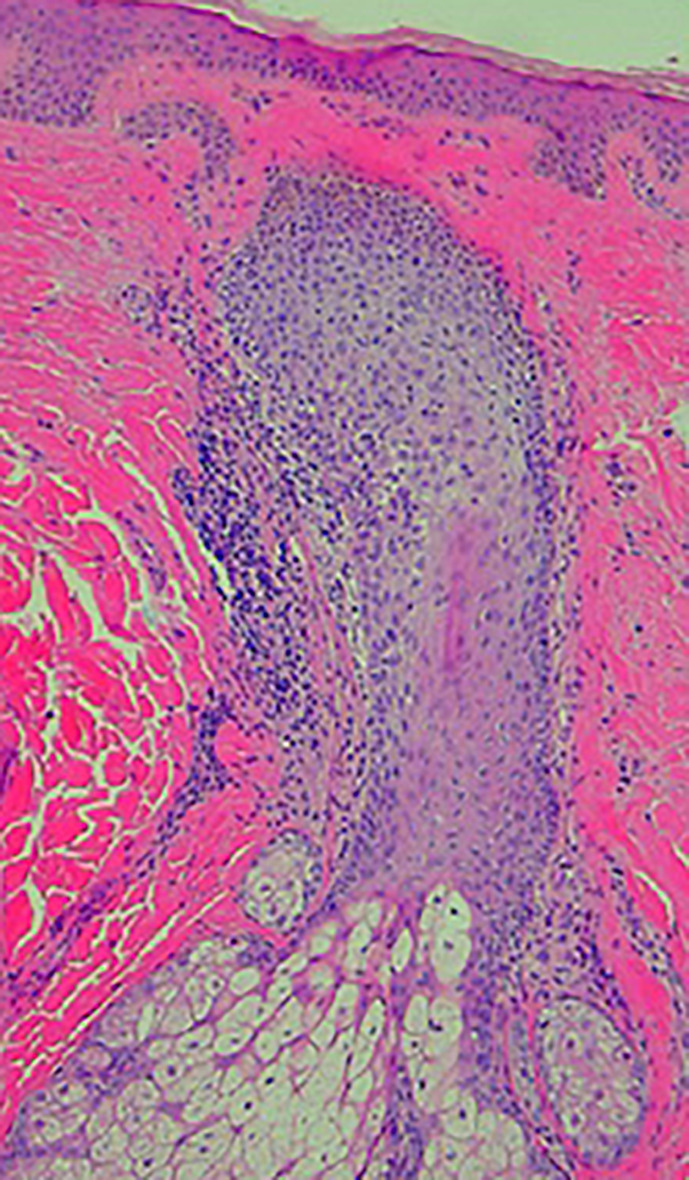

Introduction: Lichen planopilaris (LPP) is a primary lymphocytic cicatricial alopecia that represents a form of follicular lichen planus.

Case presentation: We describe a case of coexisting diffuse LPP and female pattern hair loss masquerading as diffuse alopecia areata in a 32-year-old female.

Discussion: In complex cases such as this, dermoscopy-guided vertical and horizontal biopsies from androgen sensitive and insensitive areas are helpful in increasing diagnostic yield. Prompt initiation of treatment is key to halting disease progression. Long-term follow-up is important as resolution of clinical signs does not always correlate with the absence of disease progression.